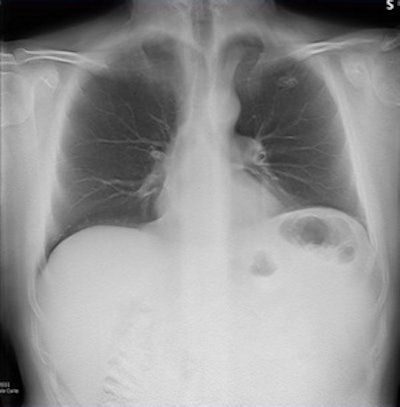

Digital tomosynthesis detected a left apical nodule in a 52-year-old male smoker. All images courtesy of Stephane Chauvie, PhD, and Dr. Maurizio Grosso.

CT confirmed the nodule in the patient and consequently he underwent surgery, which confirmed the tumoral nature of the nodule."We have very preliminary data, but we believe digital tomosynthesis is a quite good method of detection for nodules," Grosso said.